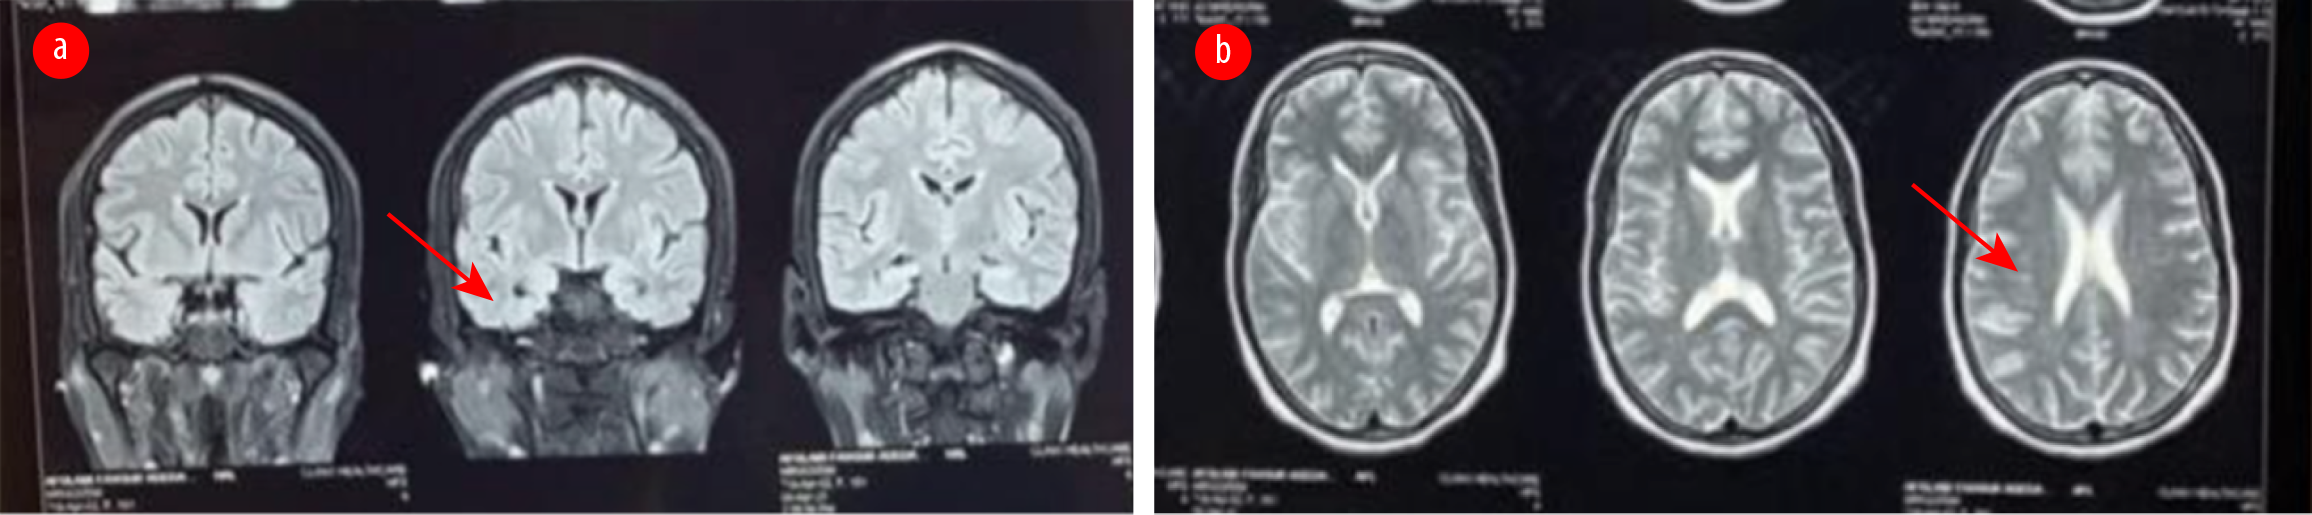

The patient was prescribed oral carbamazepine 400 mg twice daily (BD) for seizures. However, two weeks later, she returned and reported experiencing two new seizure episodes, despite her medication compliance. An assessment of breakthrough seizures was made. Carbamazepine was stopped and switched to levetiracetam 500 mg twice daily. Magnetic resonance imaging of the brain showed a few T2/FLAIR sub-centimeter white matter hyperintensities [Figure 1]. The erythrocyte sedimentation rate was 50 mm in the first hour.

Figure 1: MRI of the brain show (a) normal mesial temporal lobe (arrow) in the fluid attenuated inversion recovery coronal image, and (b) few sub-cortical white matter hyperintensities (arrow) in the T2-weighted sequence.